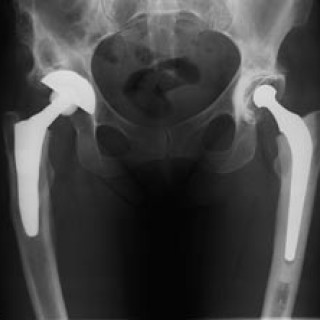

Nevroradiologi omhandler bildediagnostikk av og bildeveiledet intervensjon i sentralnervesystemet. Pasientene er i alle aldersgrupper, og flere av sykdommene er kroniske. Kunnskap om barnenevroradiologi er vesentlig for forståelsen av mange lidelser hos voksne. De viktigste bildediagnostiske hjelpemidlene (modalitetene) er CT, MR og angiografi, i tillegg til vanlig røntgen, myelografi, ultralyd, scintigrafi og positronemisjonstomografi (PET). Faget er en naturlig subspesialisering fra generell radiologi, med bakgrunn i behovet for oppbygging av kompetanse om og utvikling av høyspesialiserte...